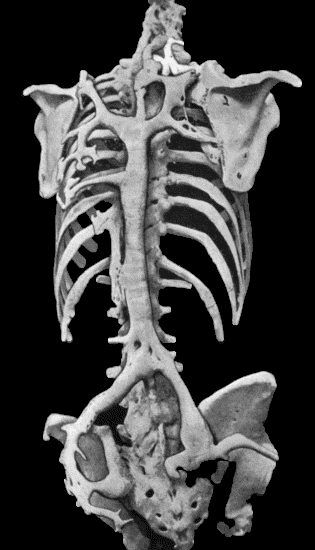

| 133. | Skeleton of Rickety Dwarf | 470 |

| 135. | Cadaver, illustrating the alterations in the Lower Limbs resulting from Ostitis Deformans | 475 |